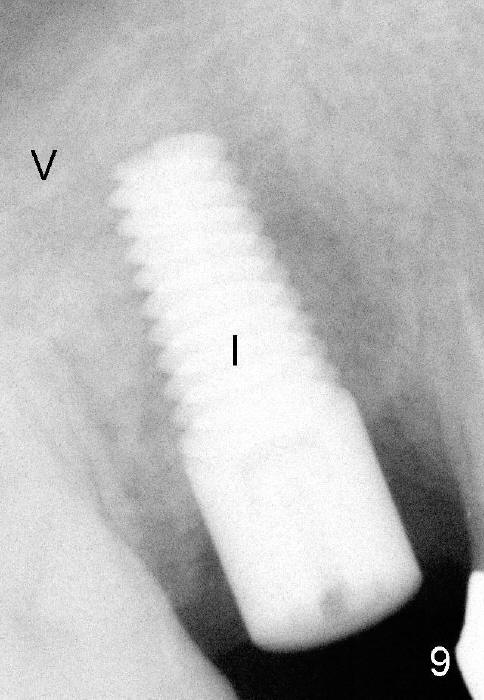

Four months after implant removal, the bony defect appears to increase (Fig.5). Reamers (Fig.6 R)and osteotome (Fig.7 O) are short of the sinus floor (arrowheads). A 5x14 mm tapered implant is placed with primary stability (Fig.8 I). The implant is placed ~ 2 mm deeper (Fig.9). No bone graft is used for sinus lift. There is no complication. The sinus floor appears to be repaired 4.5 months postop (Fig.10). Fig.11 (trimmed from panoramic X-ray) is taken 1 year 7 months post cementation. The bone remains stable 4 years 2 months post cementation (Fig.12); the mesial defect is most likely related to extraction trauma (*).